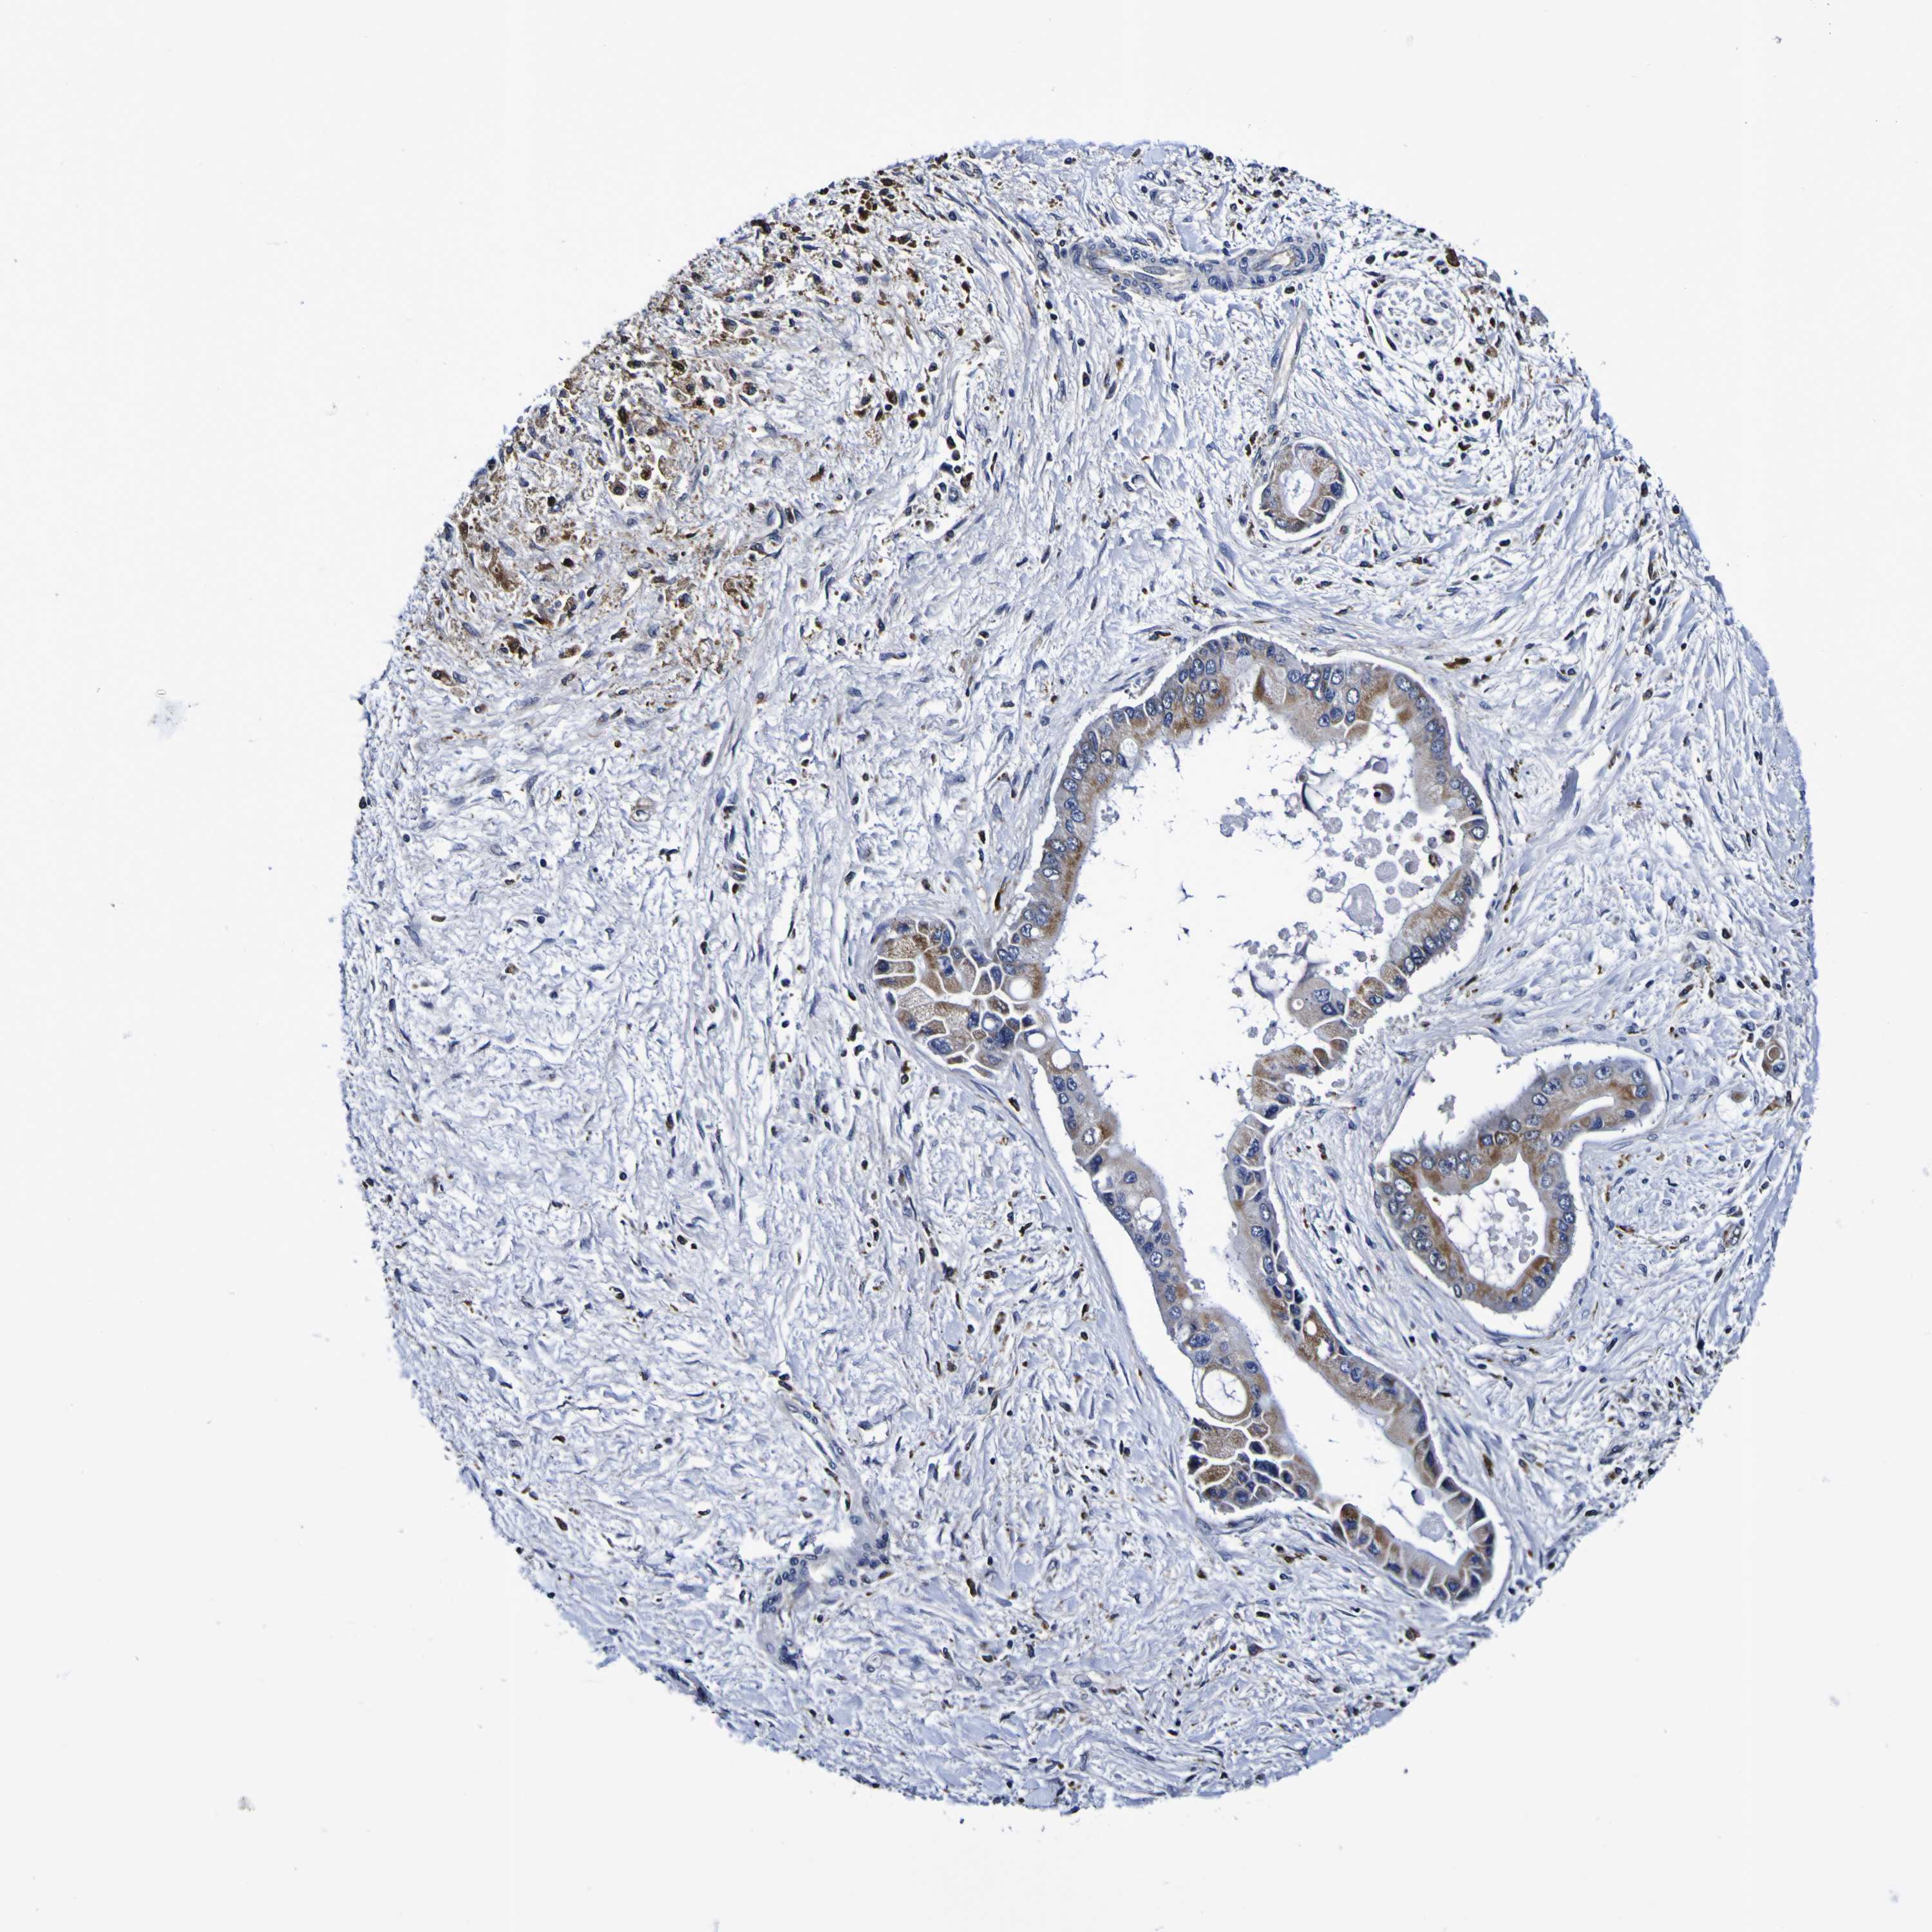

LIVER CANCER - Protein expressioni

A mouse-over function shows sample information and annotation data. Click on an image to view it in a full screen mode. Samples can be filtered based on level of antibody staining by selecting one or several of the following categories: high, medium, low and not detected. The assay and annotation is described here.

Note that samples used for immunohistochemistry by the Human Protein Atlas do not correspond to samples in the TCGA dataset.

Antibody stainingi

Antibody staining in the annotated cell types in the current human tissue is reported as not detected, low, medium, or high, based on conventional immunohistochemistry profiling in selected tissues. This score is based on the combination of the staining intensity and fraction of stained cells.

Each image is clickable and will lead to virtual microscopy that enables deeper exploration of all samples and also displays staining intensity scores, fraction scores and subcellular localization as well as patient and tissue information for each sample.

Antibody HPA044758

Antibody CAB011582

Staining

High

Medium

Low

Not detected

Intensity

Strong

Moderate

Weak

Negative

Quantity

>75%

75%-25%

<25%

None

Location

Nuclear

Cytoplasmic/membranous

Cytoplasmic/membranous,nuclear

Cholangiocarcinoma

Carcinoma, Hepatocellular, NOS